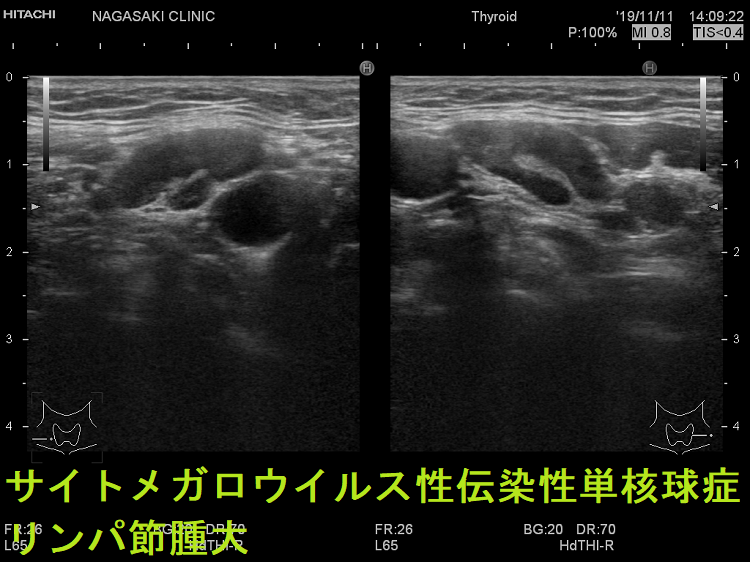

- 痛みを伴う著明な後頸部リンパ節腫脹は1〜2週頃がピークで、耳下腺の下、外側頚部まで累々と広がり、全身のリンパ節も腫大します。

- 亜急性甲状腺炎と鑑別を要する伝染性単核球症を発症